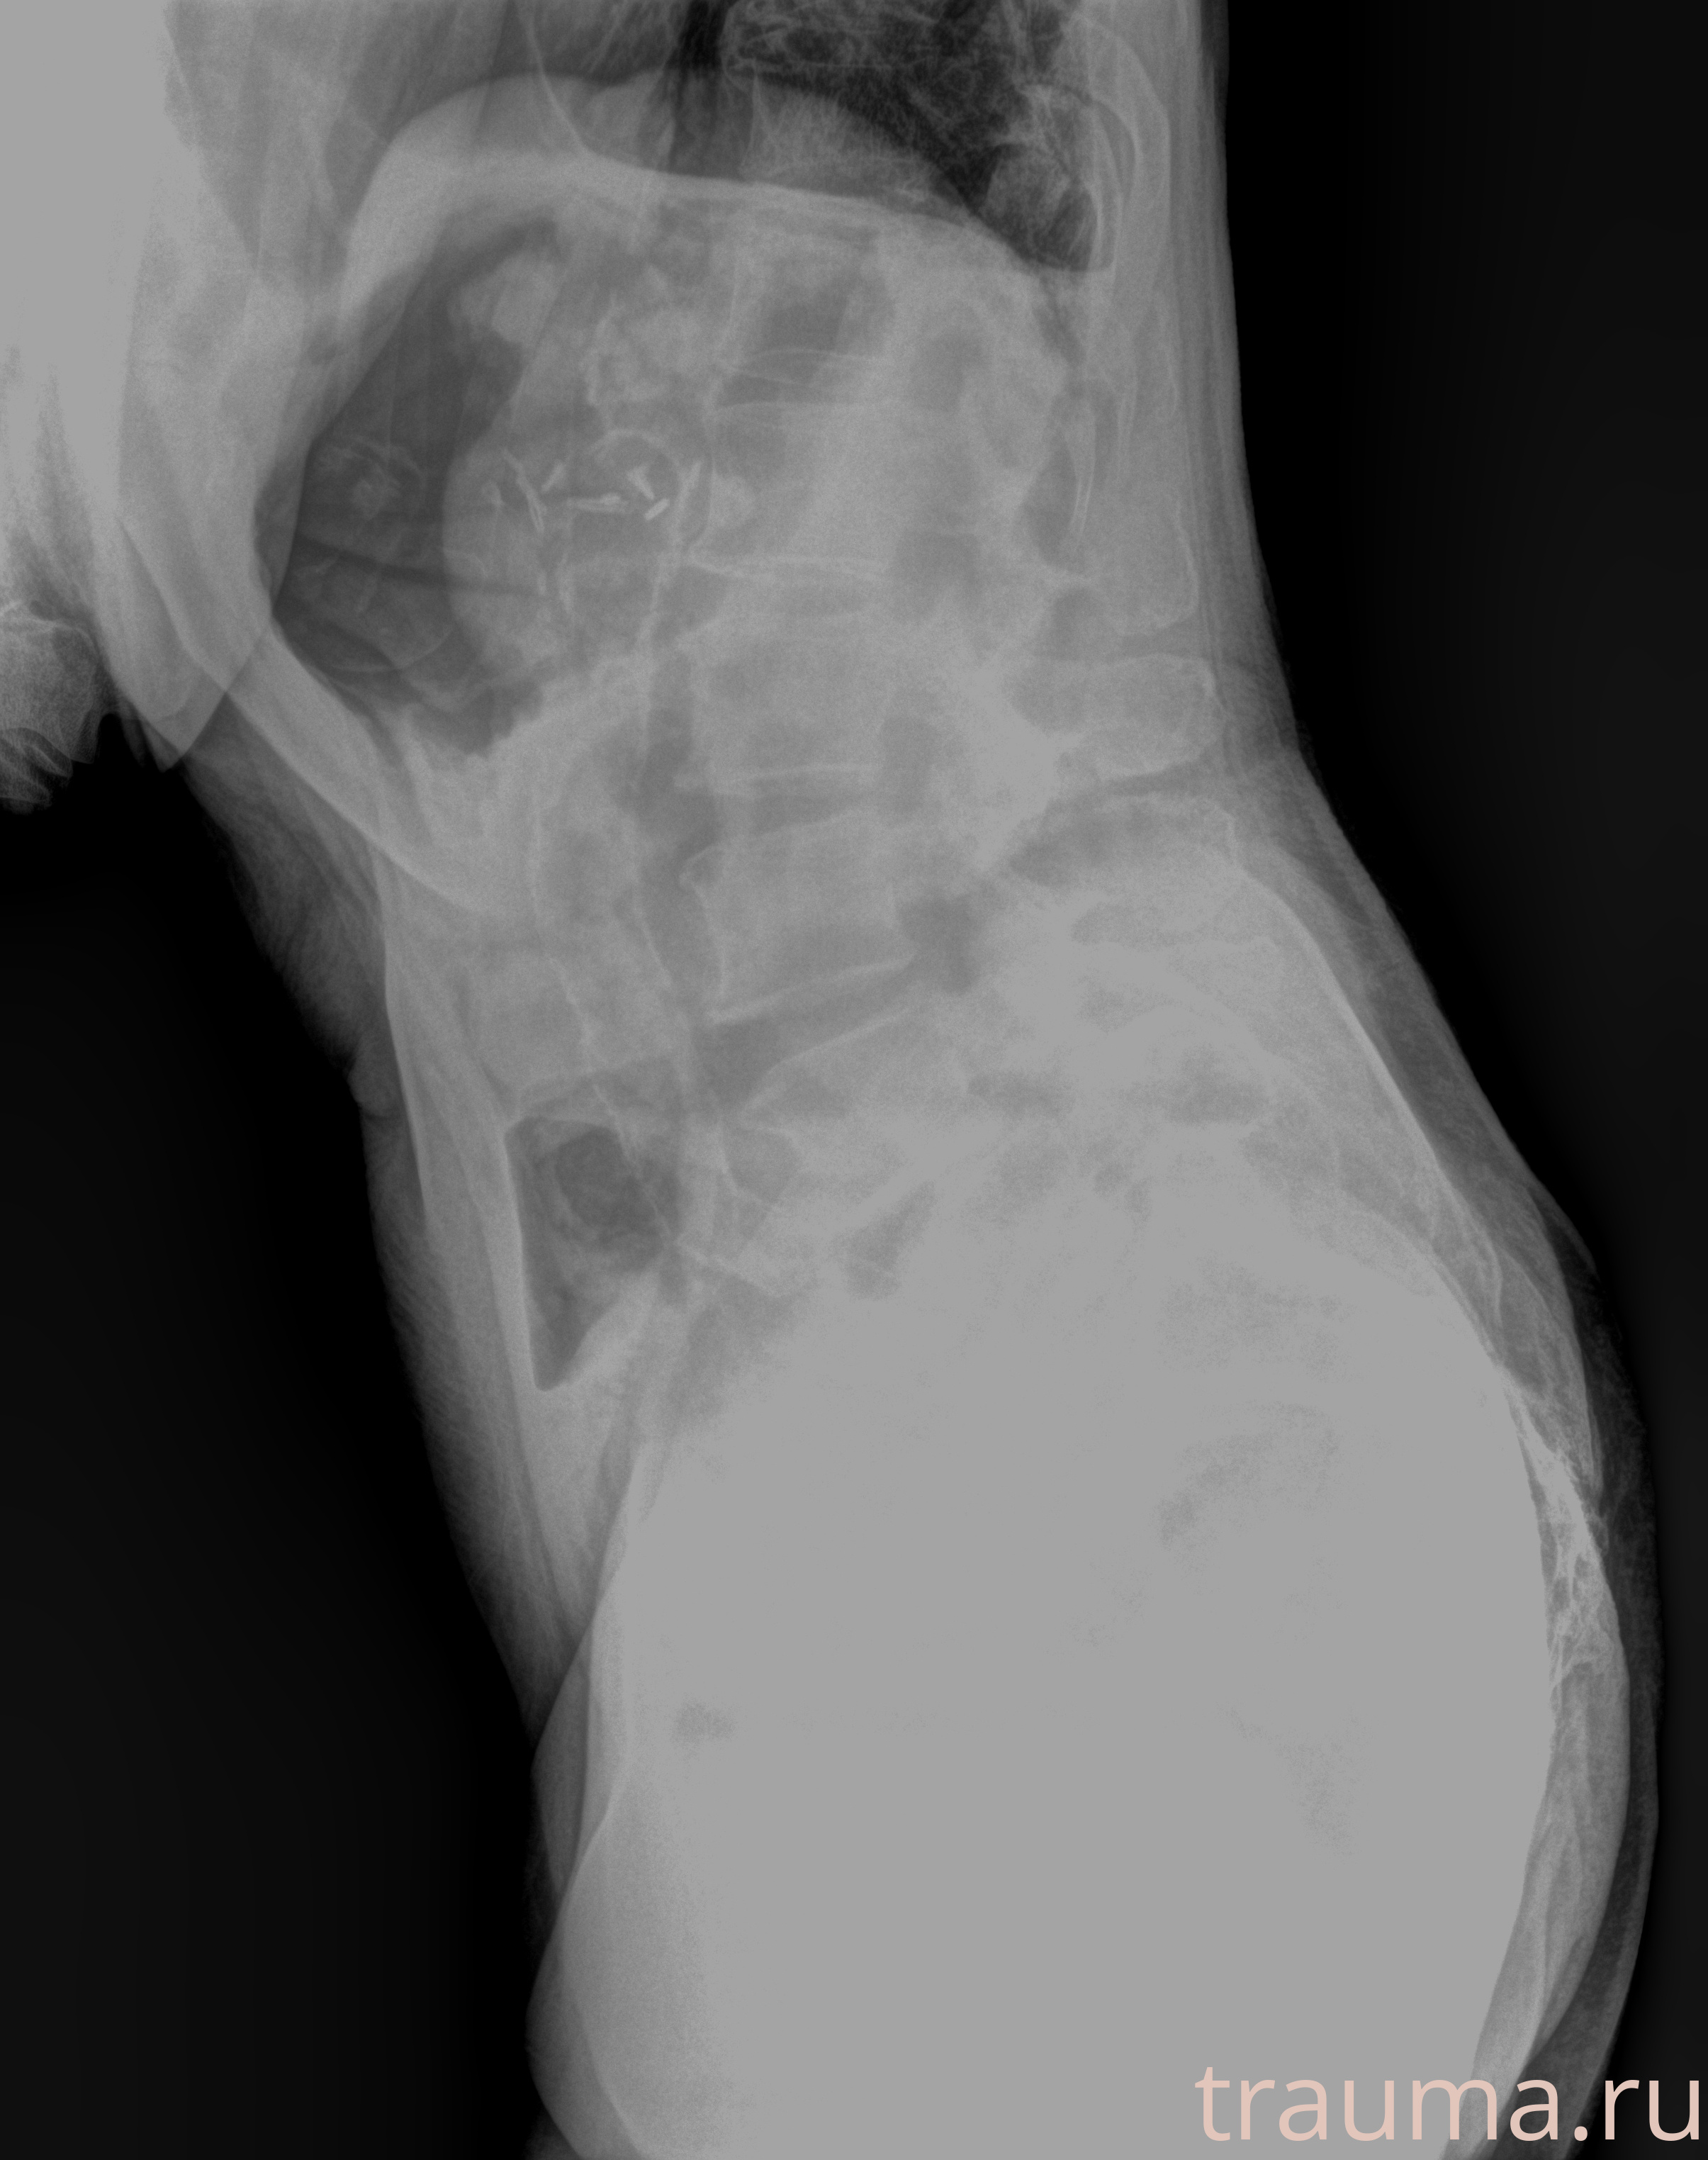

Рентгенограммы

Рентген на дому: по вашему адресу приезжает врач-рентгенолог, травматолог-ортопед с мобильным рентгеновским аппаратом, проводит диагностику травмы или заболевания, делает необходимые рентгенограммы, дает рекомендации по дальнейшему лечению. Получить качественные снимки в домашних условиях возможно благодаря уникальной методике, разработанной МосРентген Центром для института  Склифосовского